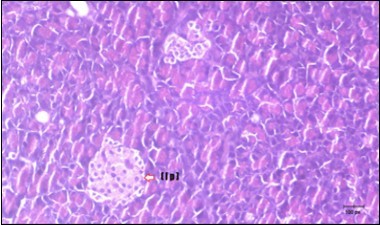

Figure 11.Photomicrogragh of pancreas section of treated rat with Glimepiride showing mildly improved of isled of Langerhans with large number of cells (dashed-arrow). (H&E) (40X).

Photomicrogragh of pancreas section of treated rat with Glimepiride showing mildly improved of isled of Langerhans with large number of cells (dashed-arrow). (H&E) (40X).